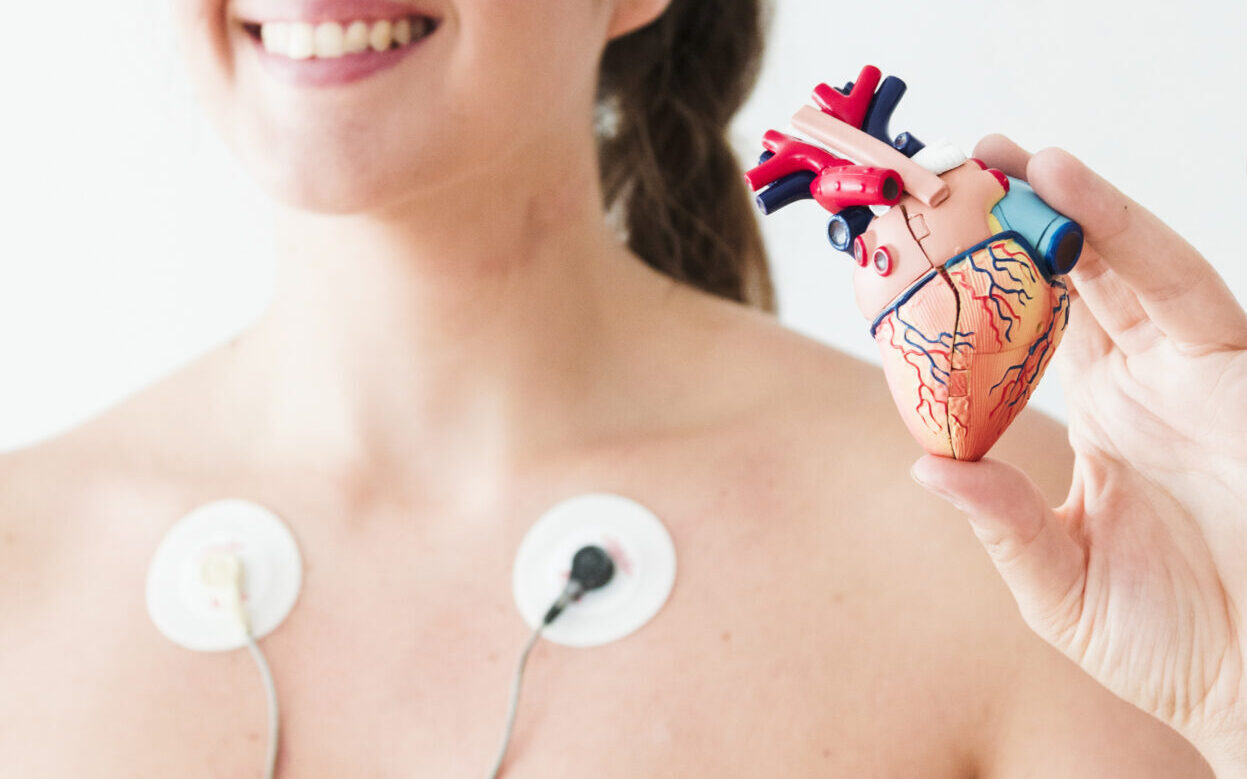

Visite specialistiche

Le nostre visite specialistiche

ll Centro Medico Diagnostic è strutturato per offrire una vasta gamma di servizi specialistici, condotti da personale esperto e altamente qualificato. Il nostro obiettivo è garantire controlli e diagnosi precise, per garantire il benessere ottimale dei nostri pazienti.